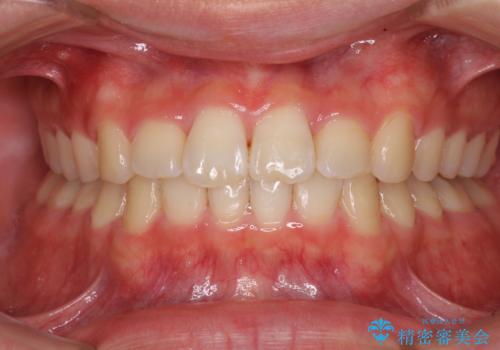

前歯のデコボコを治したい ワイヤー矯正

前歯のがたつき・すれちがい咬合を非抜歯で。流行の、格安マウスピースでは難しい、ワンランク上の治療